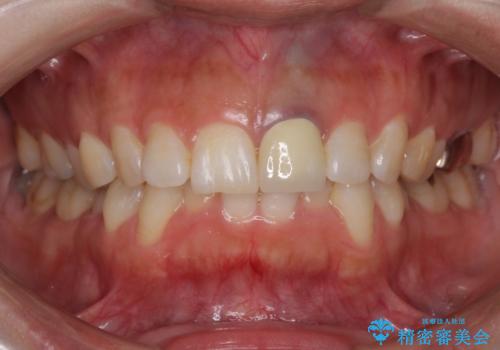

- 前歯をメタルの被せものにしており、セラミックに変えるのを希望された患者様です。

土台も金属だったため、歯がかなり黒く変色していました。

色は完全にとるのが不可能であることをご了承頂いた上で、土台と被せものの治療を行いました。

今回は歯自体が黒くなって歯茎から透けて見えている黒ずみのため、セラミック治療で改善させることは困難だというお話をしました。その上でできる範囲できれいに治療することになりました。